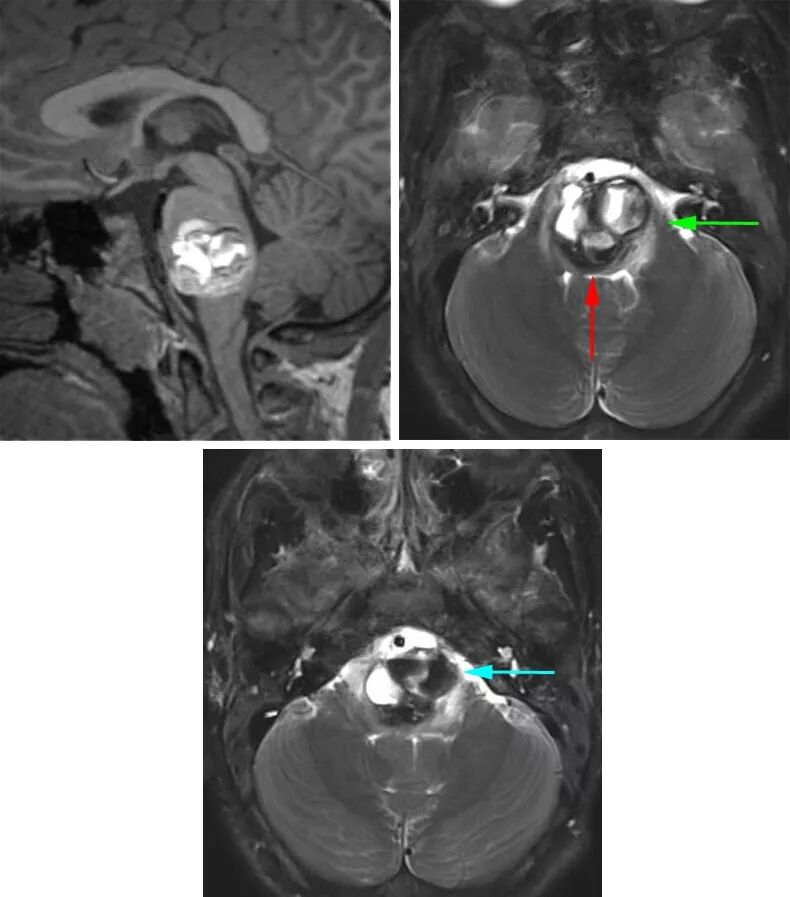

图1:图示一个桥脑后部的CM,合并明显的囊外出血(上排)。患者表现为急性轻偏瘫与颅神经功能障碍,最终行显微手术(下排)。切除的细节请参阅下面的插图。

图3:图示一个桥脑后部的CM,有一薄层完整的第四脑室底(左向箭号)。尽管最短的手术通路明显是沿第四脑室底进入,但最终选择经小脑中脚的外侧入路(右向箭号)。第四脑室底的薄层组织有重要功能,包含面丘。注意T1序列在检测神经组织方面优于T2序列,而T2序列容易被含铁血黄素引起的晕状伪影所干扰。

图12:这个桥脑延髓海绵状血管畸形主要位于脑干中央。病灶后缘有一薄层环状的正常第四脑室底,无法采用后正中入路(红色箭号)。笔者采用左侧乙状窦后入路(绿色箭号)在三叉神经与面/听神经之间切开软脑膜进入病灶的上段。此外,病灶在桥脑延髓交界水平已到达软脑膜表面,也经这个第二手术通路(蓝色箭号)切除病灶的下极。